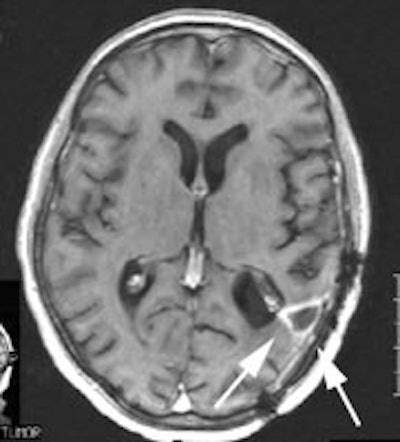

CNS radiation necrosis: The patient below had a history of a solitary brain metastasis from non-small cell lung cancer. The lesion had been resected and the patient had received radiation therapy to the area. A follow-up MR exam revealed a ring enhancing region in the left parietal-temporal area on post-gadolinium enhanced images (white arrows). A FDG PET exam revealed no tracer uptake consistent with post-surgical and post radiation change. |

|